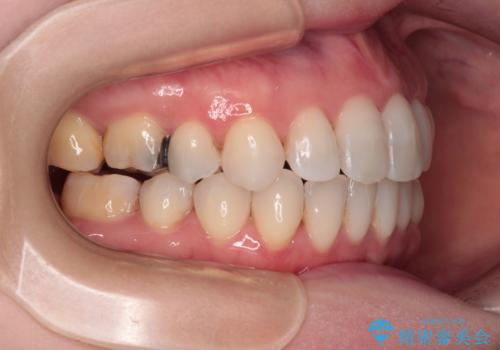

- 奥歯のむし歯を気にして来院された患者様です。

当初は右下の虫歯治療のみを希望されていましたが、虫歯治療に際して部分矯正が必要であったため、治療方法について説明をすると、全体的に歯列不正が気になっているとのことで、全顎矯正を検討することとなりました。

口元の突出感とデコボコがあり、上下左右の小臼歯4本を抜歯して矯正治療を行う方針としました。(右上は欠損のため計3本抜歯)

むし歯となっている歯は状態が悪く、将来的に抜歯となる可能性が高かったため、定石で抜歯させる小臼歯の代わりにむし歯となっている大臼歯を抜歯し、ワイヤー装置にて矯正治療を行うこととしました。